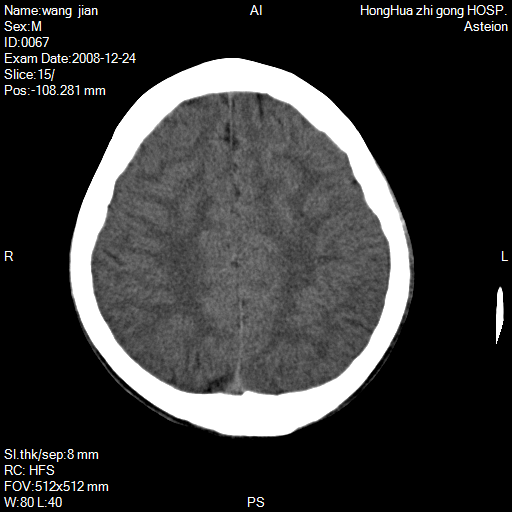

标题: CT17293:男/15/癫痫/小时有外伤史 [打印本页]

标题: CT17293:男/15/癫痫/小时有外伤史

左侧顶叶镰旁见低密度影,建议mr检查。

左顶叶大脑镰旁稍低不均质密度影,建议增强ct或mr检查

感觉额颞顶叶部分脑回很细碎,不排除异常,如小多脑回畸形,左侧中央旁小叶区确有圆形低密度区,不知是否病灶,建议mr检查

左侧顶叶镰旁见低密度影,建议mr检查。好象是伪影。

也看着了在左镰旁异常低密度灶,是占位的样子,要进一步检查清楚。